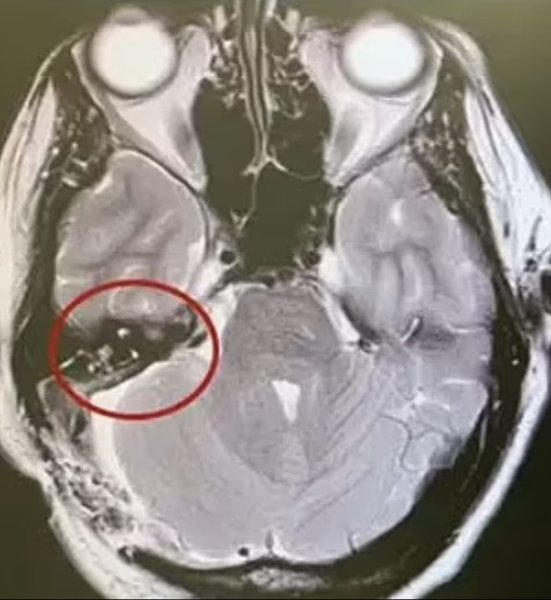

Медики смогли полностью удалить всю опухоль, но Ванакер еще 2 месяца принимала обезболивающие препараты

В ноябре 2020 года женщине сделали операцию по удалению опухоли в мозге, которая длилась долгих 9 часов. Для этого врачам пришлось удалить часть черепа и разрезать мозг пациентки. Медики смогли полностью удалить всю опухоль, но Ванакер еще 2 месяца принимала обезболивающие препараты, прежде чем боль в тройничном нерве начала отступать